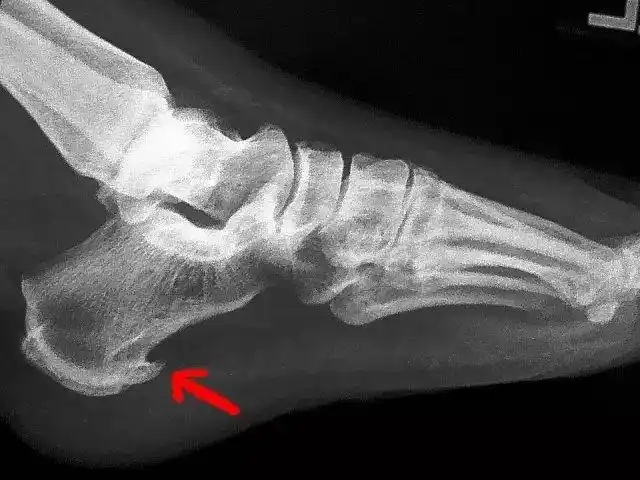

骨刺能去掉么?_骨质增生_治疗方式_日常注意事项 - 好大夫在线